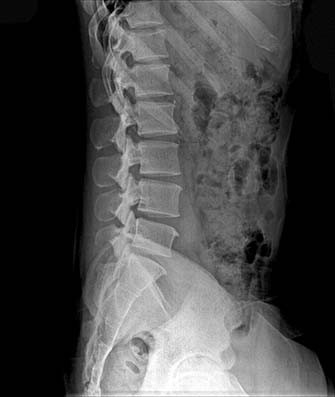

Patiënt met onbegrepen lagerugpijn heeft recht op MRI